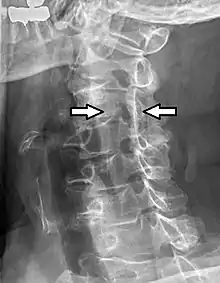

Cervical spinal nerve 4, also called C4, is a spinal nerve of the cervical segment. It originates from the spinal cord above the 4th cervical vertebra (C4). It contributes nerve fibers to the phrenic nerve, the motor nerve to the thoracoabdominal diaphragm. It also provides motor nerves for the longus capitis, longus colli, anterior scalene, middle scalene, and levator scapulae muscles. C4 contributes some sensory fibers to the supraclavicular nerves, responsible for sensation from the skin above the clavicle.[1] C4 and C5 are the areas that see the highest amount of cervical spine trauma.[2]